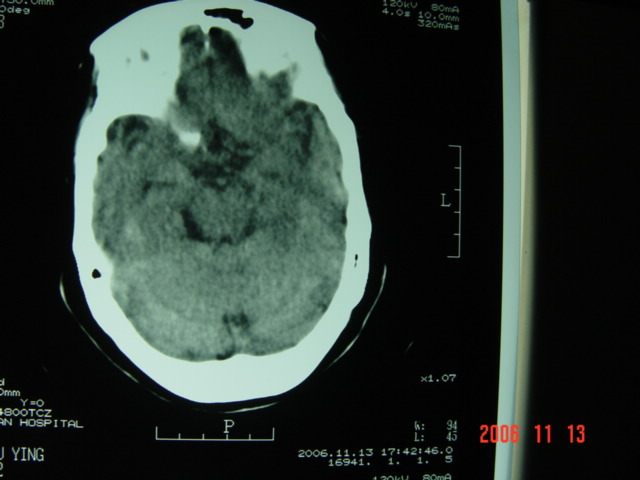

失语及右侧肢体无力3小时

左侧大脑半球与对侧相比较密度普遍密度降低,结合临床首先考虑是脑梗塞早期,必要时复查或mri。

左侧脑表面脑变窄,左外侧裂池受压变窄。

左侧大脑半球密度减低,左外侧裂消失。脑梗塞急性期

左侧侧裂池消失,脑沟变浅.典型的一侧大脑半球缺血改变.可以诊断:左侧大面积脑梗塞.

左侧大脑半球大片密度减低影,脑沟变浅,外侧裂变窄,中线结构无明显移位。左侧大面积脑梗塞,大脑中动脉堵塞所致,愈后不好呀!应早期溶栓啊。

典型的左侧大脑半球早期缺血性脑梗塞(符合大脑前动脉、中动脉、大脑后动脉供血区。)

左侧颞顶叶皮层与白质呈大片状低密度影,左侧脑室颞角,及侧裂池受压变小.中线居中.

意见:左侧颞顶叶大面积梗塞(脑膜中动脉梗塞),

典型的左侧大脑半球缺血性脑梗塞早期表现[左侧大脑半球皮质密度减低与脑白质密度一致(脑皮质征),左侧豆状核轮廓模糊,密度与脑白质一致(豆状核征),结合临床有失语及右侧肢体无力3小时]。